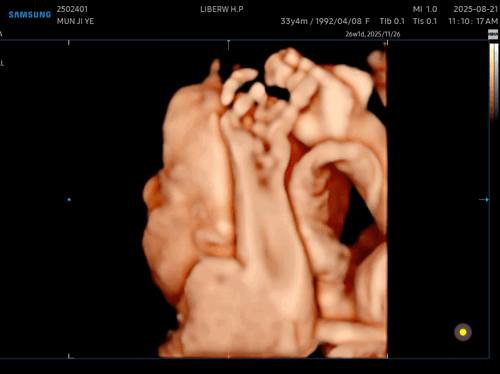

아쉽게도

사탕이는 얼굴을 가리고 있었다🥲

안쪽에 팔로 얼굴 가리고 숨은 사탕

이 상태로 찍어봤지만,,,!

여기까지가 최선이었다^^,,,

또르르🥲

얼굴은 숨어버리고

손이랑 발만 보여줌 ㅎㅎㅎㅎㅎ

그것도 웅크리고 숨어있어서

손이랑 발도 제대로 못 찍고,,,